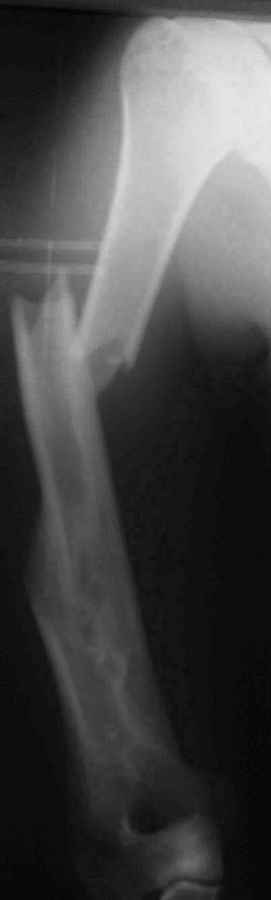

[Ortho] Результат консервативного лечения короткого косого перелома диафиза плеча врачами общей практики в условиях развивающейся страны у больного low social class

Последний перелом плеча – ДТП 2 мес назад. В связи с дефицитом как специалистов – ортопедов, так и операционного времени в принципе больной был осмотрен в приемном покое врачом общей практики, наложена U-образная гипсовая повязка и отправлен домой. Я впервые увидел больного через 6 нед после травмы, сделал снимки и снял повязку. Фотографии больного  - 2 мес после травмы. снимки - при травме и через 6 недель

Вывод: Если плечо не трогать, оно нормально срастается.

Тот же самый вывод наукообразно: данное клиническое наблюдение свидетельствует, что консервативное лечение переломов диафиза плеча является патофизиологически оптимальным, приводит к удовлетворительному функциональному результату и явлеяется наиболее экономически щадащим как для больного, так и для системы государственного здравоохранения в целом.